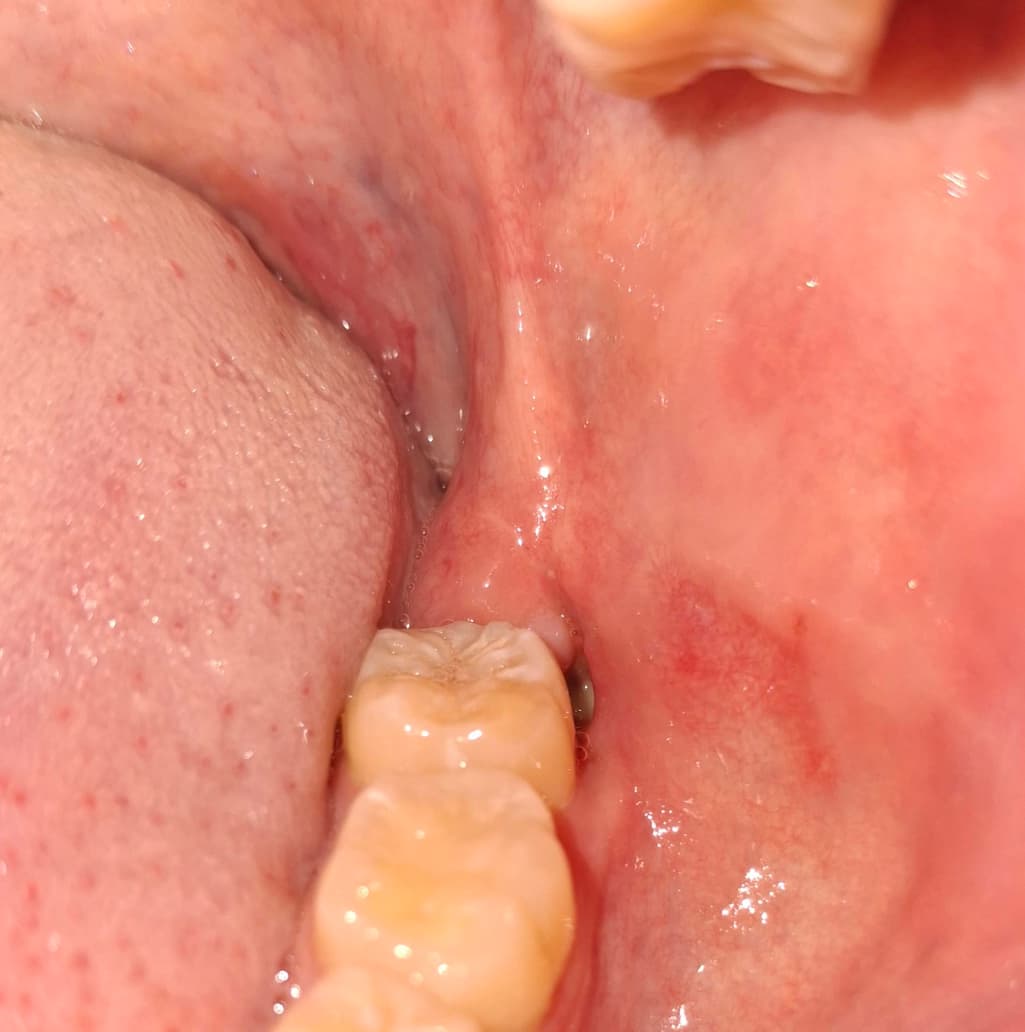

사랑니 발치 이후 20일 가량 경과 하였고, 그 과정에서 발생한 구멍의 끝에 하얀색 조직이 생겼습니다.

통증은 없습니다만, 궁금하여 이렇게 올려봅니다.

아직 사랑니 발치를 한곳이 다 아물지 않은 상태 같습니다. 아물면서 생기는 현상이니 걱정하지 않으셔도 될것같습니다.

아직 잇몸이 완전히 아물지 않아서 그렇게 보이는 것으로 시간이 지나면 다 회복될 것입니다.

사랑제를 발치하면 발치한 부위가 아무나 과정에서 하얀색 가피가 형성될 수 있습니다. 크게 문제가 되는 것은 아니니 걱정하지 않으셔도 될 것으로 생각됩니다. 발치를 했다면 발치한 부위가 자극이 되지 않도록 하는 거에 좋습니다.